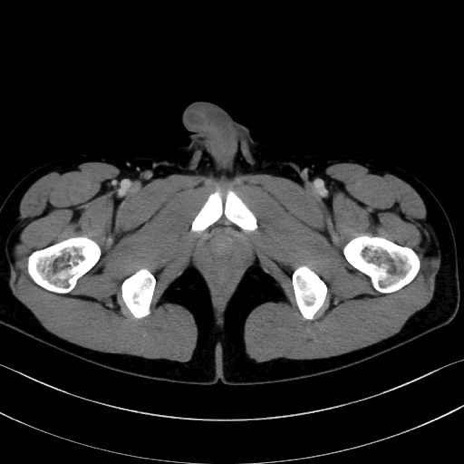

梨状筋(piriformis muscle) のCT画像の解剖

梨状筋 (Piriformis)

内閉鎖筋 (Obturator internus)

外閉鎖筋 (Obturator externus)

大腿方形筋 (Quadratus femoris)